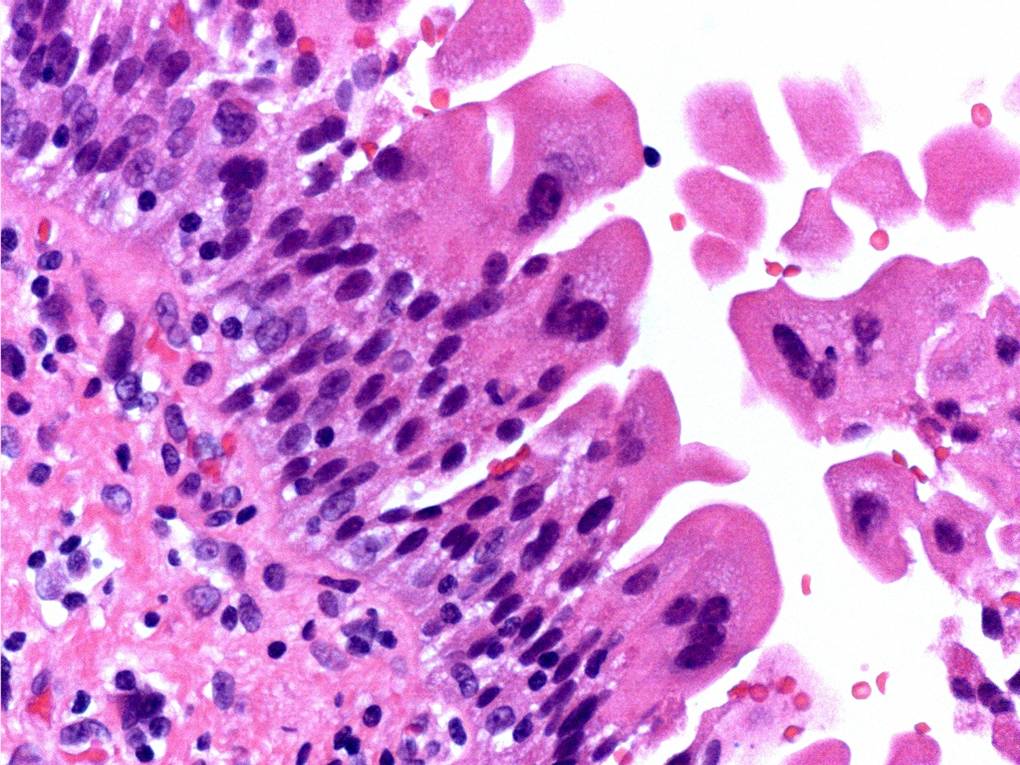

Consensus grade: Reactive atypia

Case description (by case creator):

The main change here is ‘degenerative’ nuclear atypia in a rather unusually prominent umbrella cell layer. The underlying urothelium shows mild reactive changes in places with some chronic inflammation in the lamina propria.